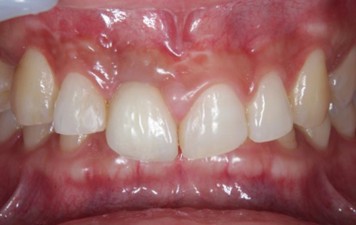

20代 男性

治療前

治療後

治療後- リスク・副作用

(薬・注射・レントゲン・CT・データ分析・骨造成・サージカルステント・血液検査・仮歯) - 年齢/性別

- 20代/男性

- 患者の具体的な症状

- 1年前に左上12 右上1の根の治療をし、その後放置していたら、左上2が破折した。

左上2インプラント補綴 左上1右上1オールセラミック装着。

歯根破折と虫歯による痛み、審美障害を主訴として来院。 - 検査方法

- コーンビームCT、レントゲン撮影

- 診断結果

- 左上2 歯根破折

- 治療詳細

- 左上抜歯後、インプラント埋入1本

骨造成あり 局所麻酔

インプラント治療後、左上1右上1セラミック修復2本 - 通院回数

- 9回

- 治療期間

- 12か月